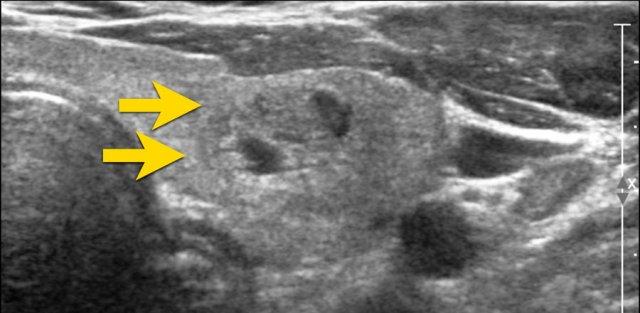

Nốt Không Rõ Ranh Giới

Trong hình ảnh được cung cấp, chỉ có các đoạn nhỏ của bờ nốt là có thể nhận thấy được (được chỉ ra bởi các mũi tên).

Phần lớn bờ nốt không phân biệt được với nhu mô tuyến giáp.

Điểm TI-RADS: 0 điểm.